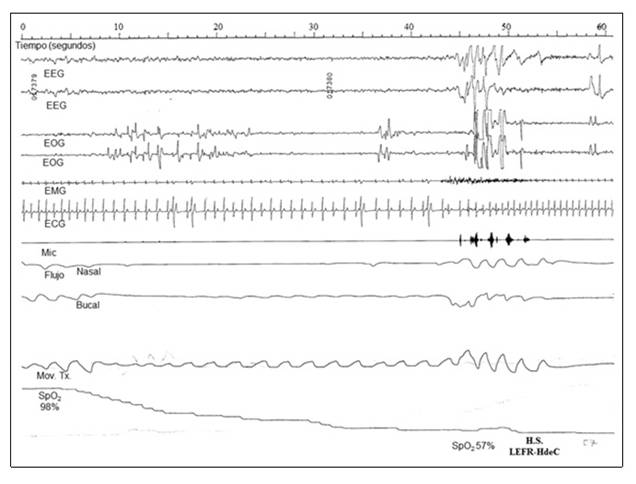

La polisomnografía incluyó registro simultáneo de: video con luz infrarroja, posición corporal, electroencefalograma, electrooculograma, electromiograma mentoniano y de miembros, micrófono en el cuello, electrocardiograma, flujo aéreo nasal y bucal (termistor), flujo nasal (presión), movimientos respiratorios abdominales y torácicos (sensor piezoeléctrico) y saturación de oxígeno del pulso. La estadificación del sueño se realizó en forma manual mediante lectura del registro diferida, siguiendo criterios estandarizados de Rechtschaffen y Kales12. A partir de 2007 se usó la actualización de la estadificación de la AASM13. Para la clasificación de los diagnósticos se utilizó la Clasificación Internacional de Trastornos del Sueño14.

Fue posible revisar los datos de las polisomnografías de noche completa (Figura 11) de 1496 pacientes con SAHOS, cuyos datos se presentan en la Tabla 9.

Figura 11: Ejemplo de registro polisomnográfico de una apnea del sueño de mecanismo obstructivo. En el panel superior: tiempo en segundos. El electroencefalograma (EEG) y el electro-óculograma (EOG) muestran Estadio del sueño R (movimientos oculares rápidos) con hipotonía muscular en el electromiograma mentoniano (EMG). Durante la apnea se observa ausencia de señal en el micrófono del cuello (Mic) y el Flujo nasal y bucal, respiratorio con aumento progresivo del esfuerzo torácico (Mov Tx) y desaturación de oxígeno (SpO2) de 98% a 57%. En el ECG se aprecia enlentecimiento de la frecuencia. Luego de 44s se produce un despertar (activación de EMG y EEG) con recuperación de la ventilación (5 respiraciones), ronquido y taquicardia. Posteriormente, nueva conciliación del sueño y comienzo de otra apnea.